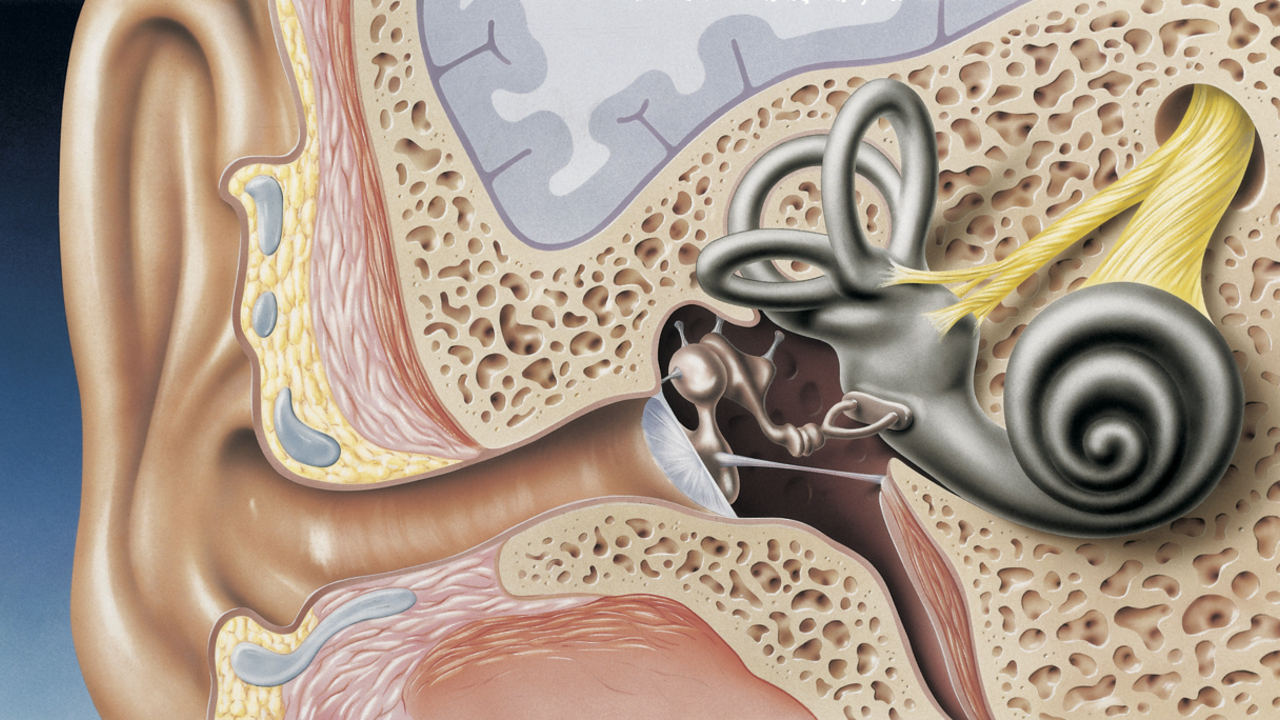

Современные слуховые аппараты при сенсоневральной тугоухости